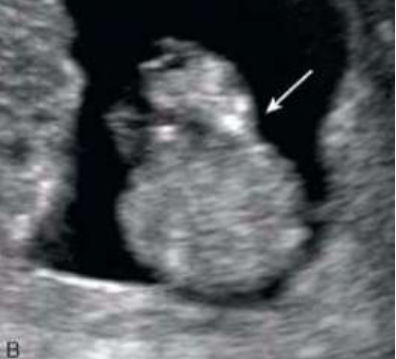

Achados ultrassonográficos de estruturas herniadas através do anel umbilical, recobertas por membrana e inserção do cordão no ápice dessa massa, são compatíveis com o diagnóstico de onfalocele.